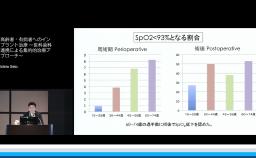

高齢者の咬合力回復は,栄養摂取や全身の筋力維持に貢献できる.インプラント治療もQOL向上に大きく寄与できる可能性を有する.一方,術後の全身の健康状態の変化に対応したメンテナンスを術前から考える必要がある.